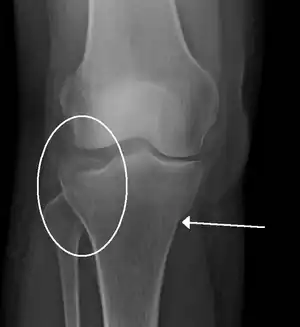

| A tibial plateau fracture | |

- Tibial plateau fracture

- Segond fracture - an avulsion fracture of the lateral tibial condyle